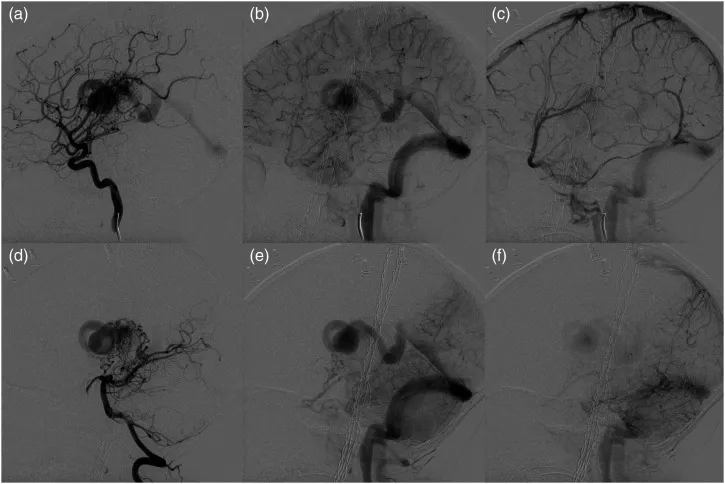

一次发病两年后,即7岁时,随访MRI和导管血管造影(图4)证实在左丘脑中形成了一个新生的脑动静脉畸形,就在先前治疗过的病变内侧。血管造影证实了左丘脑动静脉畸形流入先前观察到的DVA的扩张囊中。bAVM病灶由左前脉络膜动脉、左后脉络膜动脉、外侧豆纹动脉、丘脑穿通动脉和MCA跨侧裂供血血管供血。此时的体格检查显示右臂痉挛性无力和右手震颤。

图4:一次发病2年后接受放射外科手术后的血管造影